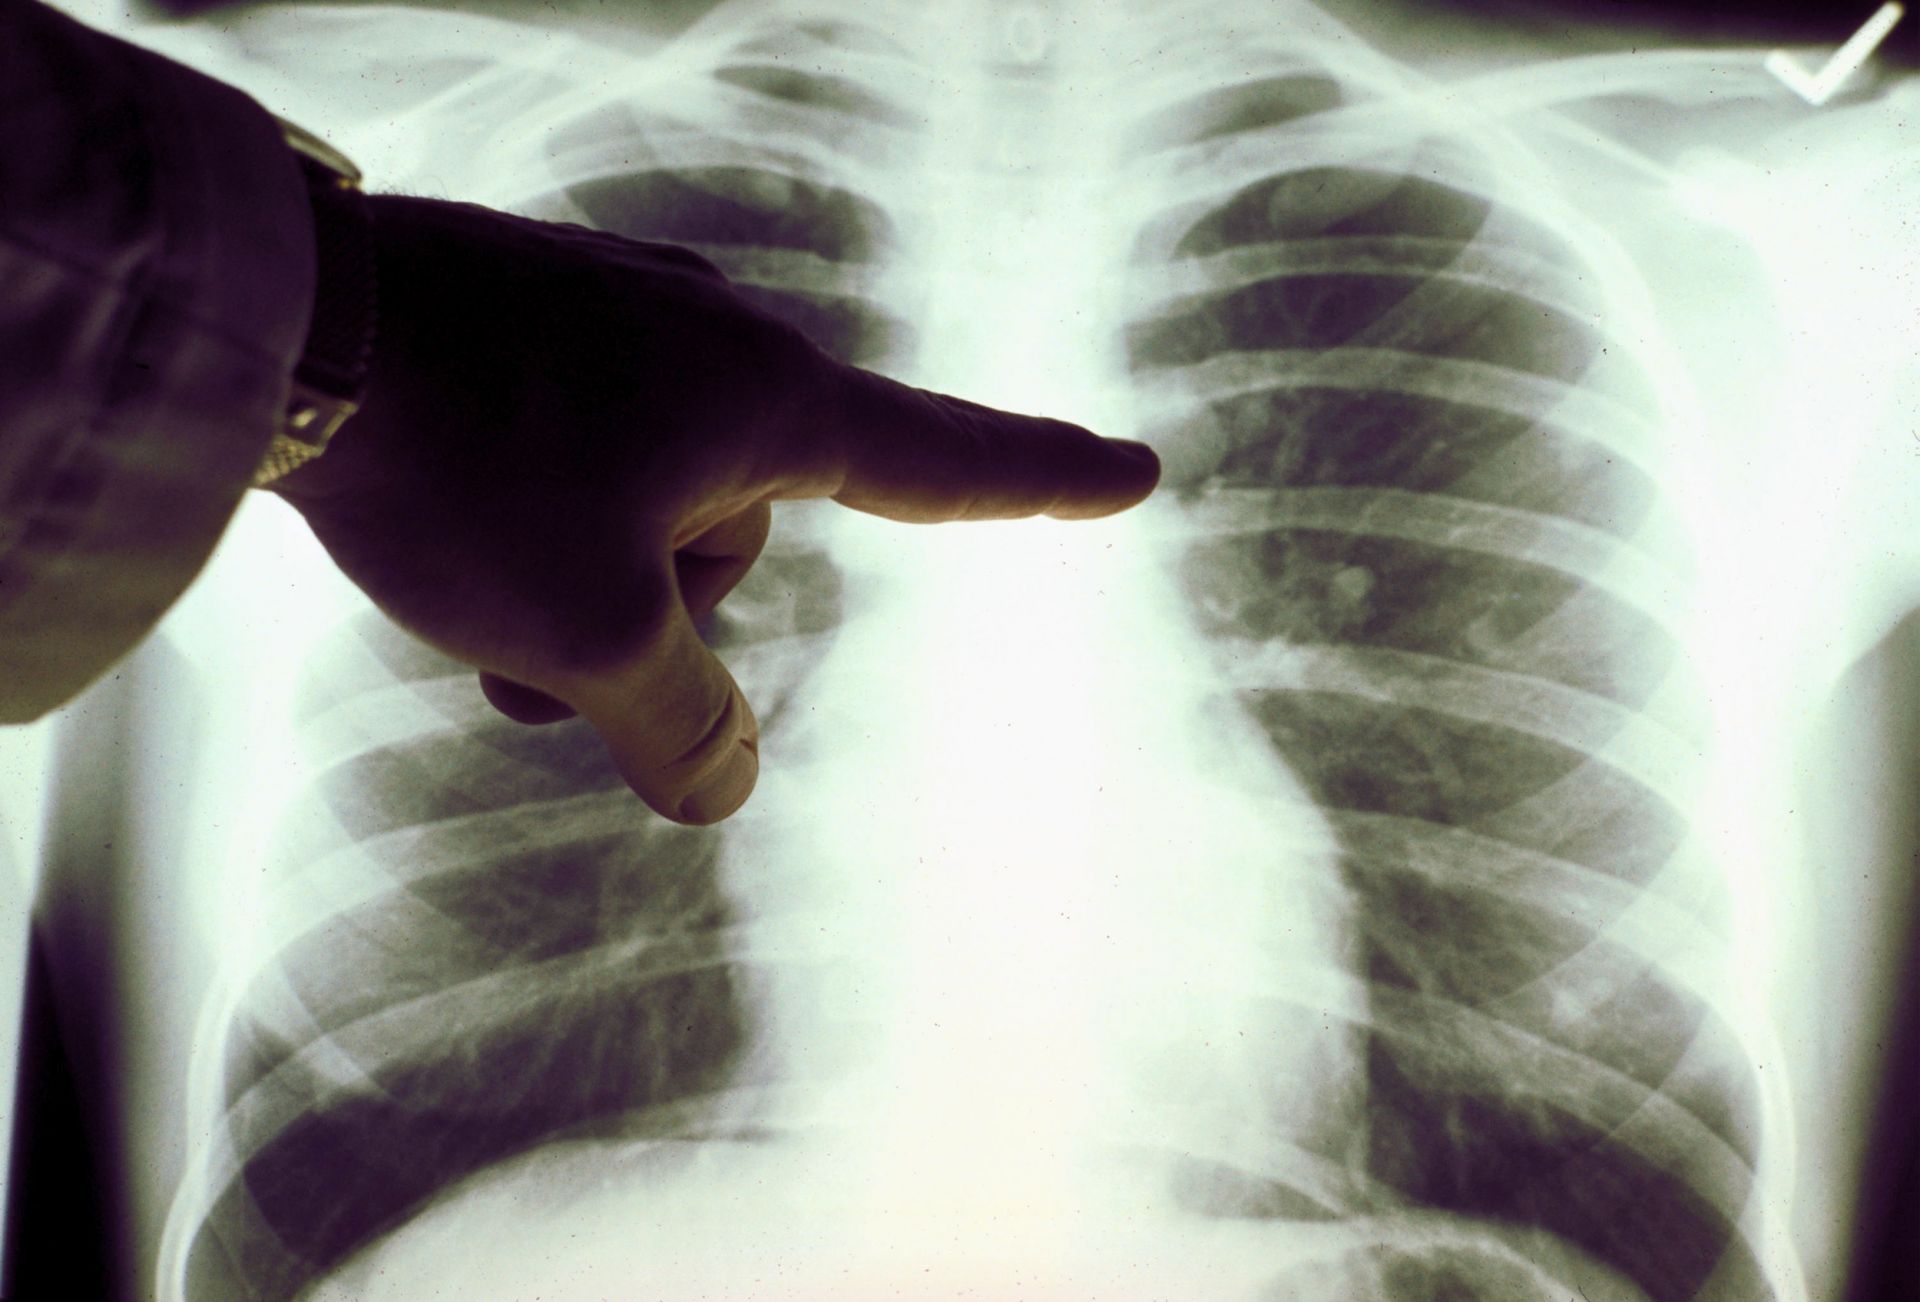

Οι καπνίζοντες και μη, γνωρίζουν τους κινδύνους του καπνίσματος, διότι τα τσιγάρα ευθύνονται για 7 στις 10 περιπτώσεις καρκίνου του πνεύμονα.

Εάν λέτε σθεναρά «όχι» στο τσιγάρο, οι πιθανότητες να γλιτώσετε από αυτή την ασθένεια είναι πολύ μεγαλύτερες.

Αλλά είναι ακόμα πιθανό να αναπτύξετε καρκίνο του πνεύμονα, ακόμα και αν απέχετε από την πιο κοινή του αιτία. Όπως ενημερώνει η Sun, ο ερευνητικός οργανισμός Cancer Research UK σημειώνει πως έως και 14% των ατόμων με αυτόν τον καρκίνο στη Βρετανία δεν έχουν καπνίσει ποτέ.

Κατά κάποιον τρόπο, ο καρκίνος του πνεύμονα σε μη καπνιστές μπορεί να θεωρηθεί ξεχωριστή ασθένεια από αυτόν που προσβάλλει τους καπνίζοντες, καθώς έχει μοναδικά μοριακά και βιολογικά χαρακτηριστικά και ανταποκρίνεται διαφορετικά στη θεραπεία.

Οι τύποι καρκίνου του πνεύμονα

Η Anne Chiang, ογκολόγος και χειρουργός θώρακος στο πανεπιστημιακό νοσοκομείο Smilow του Yale, εξήγησε: «Παλιά νομίζαμε ότι όλοι οι καρκίνοι του πνεύμονα ήταν ίδιοι, αλλά τώρα καταλαβαίνουμε ότι υπάρχουν διαφορετικά είδη».

Στην πραγματικότητα, οι περισσότεροι μη καπνιστές διαγιγνώσκονται με έναν μη μικροκυτταρικό τύπο της ασθένειας γνωστό ως αδενοκαρκίνωμα, το οποίο συχνά ξεκινά από τις βλεννογόνους των πνευμόνων.

Αντίθετα, οι καπνιστές τείνουν να αναπτύσσουν έναν τύπο ακανθοκυτταρικού καρκινώματος μη μικροκυτταρικού καρκίνου του πνεύμονα, σύμφωνα με την ειδικό του Yale.

Τα συμπτώματα του αδενοκαρκινώματος

Οι περισσότεροι μη καπνιστές δεν εκδηλώνουν πρώιμα σημάδια καρκίνου του πνεύμονα, πράγμα που σημαίνει ότι συχνά δεν διαγιγνώσκονται μέχρι να εξαπλωθεί. Αλλά μερικοί παρατηρούν συμπτώματα στα αρχικά στάδιά της, σύμφωνα με την Δρ. Chiang.

Αυτά είναι παρόμοια με τα συμπτώματα στους καπνιστές και μπορεί να περιλαμβάνουν τα ακόλουθα:

- Επίμονος βήχας που επιδεινώνεται με την πάροδο του χρόνου

- Βήχας με αιμόπτυση

- Στηθάγχη

- Δύσπνοια

- Συριγμός

- Βραχνάδα

- Απώλεια όρεξης

- Απώλεια βάρους

- Κόπωση

- Δυσκολία στην κατάποση

- Πρήξιμο στο πρόσωπο ή στον λαιμό

- Υποτροπιάζουσες πνευμονικές λοιμώξεις